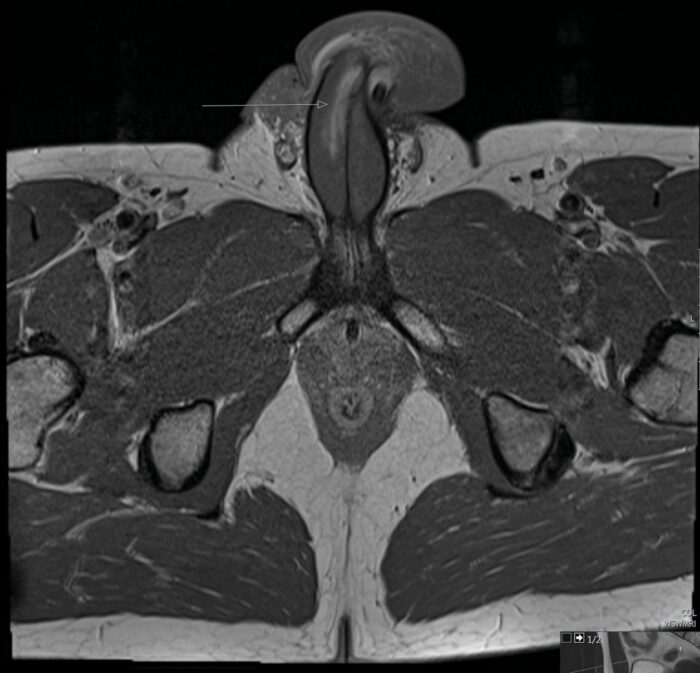

Aber in diesem Fall spaltet es die Tunica albuginea – die Schutzschicht um den Schwellkörper, die Blut in diesen Bereich pumpt.

Es gibt keine Knochen im Penis, aber Brüche treten normalerweise auf, wenn der Penis eines Mannes aus seinem Partner rutscht und plötzlich gebogen wird, was zu schmerzhaften Schwellungen führen kann.

Blut fließt in die Schwellkörper, die entlang des Penis verlaufen und ihn während einer Erektion hart machen.